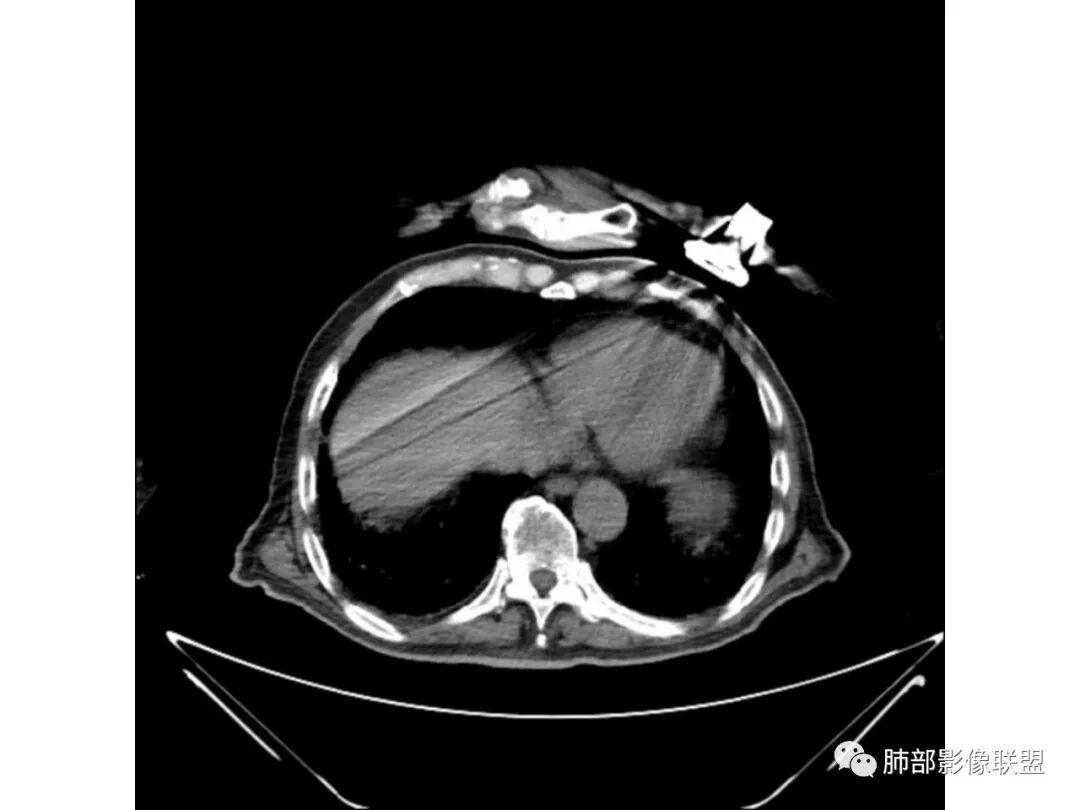

老年男性,有糖尿病病史,右侧胸廓塌陷,肺容积缩小,右肺上叶片状实变密度影及高密度影,边缘模糊,内可见支气管充气征及多发虫蚀样空洞,考虑结核可能大。肝脏只有一层,看上去正常